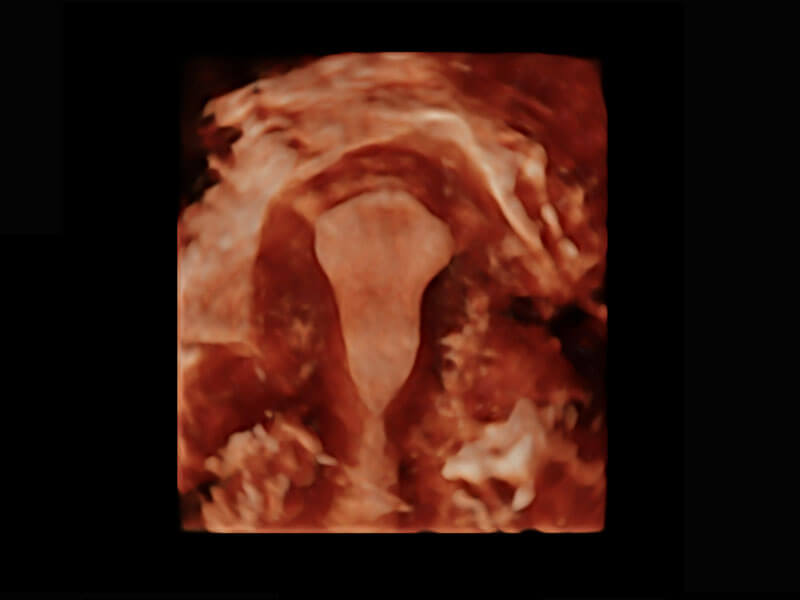

P60在胎儿早孕期超声筛查中为您带来优异的图像质量。

早孕-胎心

高分辨率容积成像-早孕胎儿

胎儿体循环

光影成像-孕囊